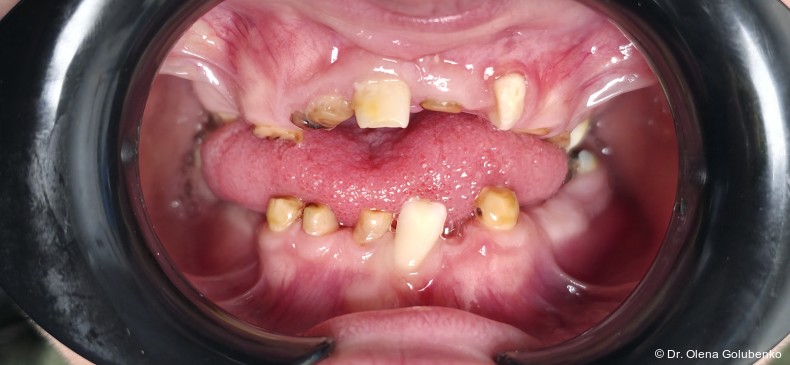

Der vorliegende Beitrag entstand aus einer kollegialen Anfrage: Eine 17-jährige Patientin mit ausgeprägten dentalen Auffälligkeiten wurde zur kieferorthopädischen Beratung überwiesen (Abb. 1a–c). Trotz zahlreicher vorangegangener zahnärztlicher Behandlungen war bis zu diesem Zeitpunkt keine syndromale Diagnose gestellt worden. Erst durch die sorgfältige Erhebung der allgemeinen und zahnmedizinischen Anamnese, die klinische Untersuchung sowie die gezielte Auswertung der dreidimensionalen Bildgebung ließ sich ein charakteristisches Muster erkennen. Auf dieser Grundlage ergab sich aus kieferorthopädischer Sicht der begründete Verdacht auf eine cleidokraniale Dysplasie, der die Vielzahl der dentalen, skelettalen und fazialen Befunde erstmals in einen schlüssigen klinischen Zusammenhang stellte.

Das dentale Erscheinungsbild ist häufig sehr charakteristisch und erlaubt bereits früh einen Syndromverdacht. Typische Befunde sind:

• lang anhaltende Persistenz der Milchzähne

• ausgeprägte Retention der bleibenden Zähne

• multiple überzählige Zähne

• fehlende oder stark verzögerte spontane Zahndurchbrüche

• Engstände und Fehlstellungen

Die dreidimensionale Bildgebung zeigt meist eine hohe Anzahl nicht durchgebrochener permanenter und überzähliger Zähne, die in unterschiedlicher Lage im Kiefer verbleiben (Abb. 3+4).